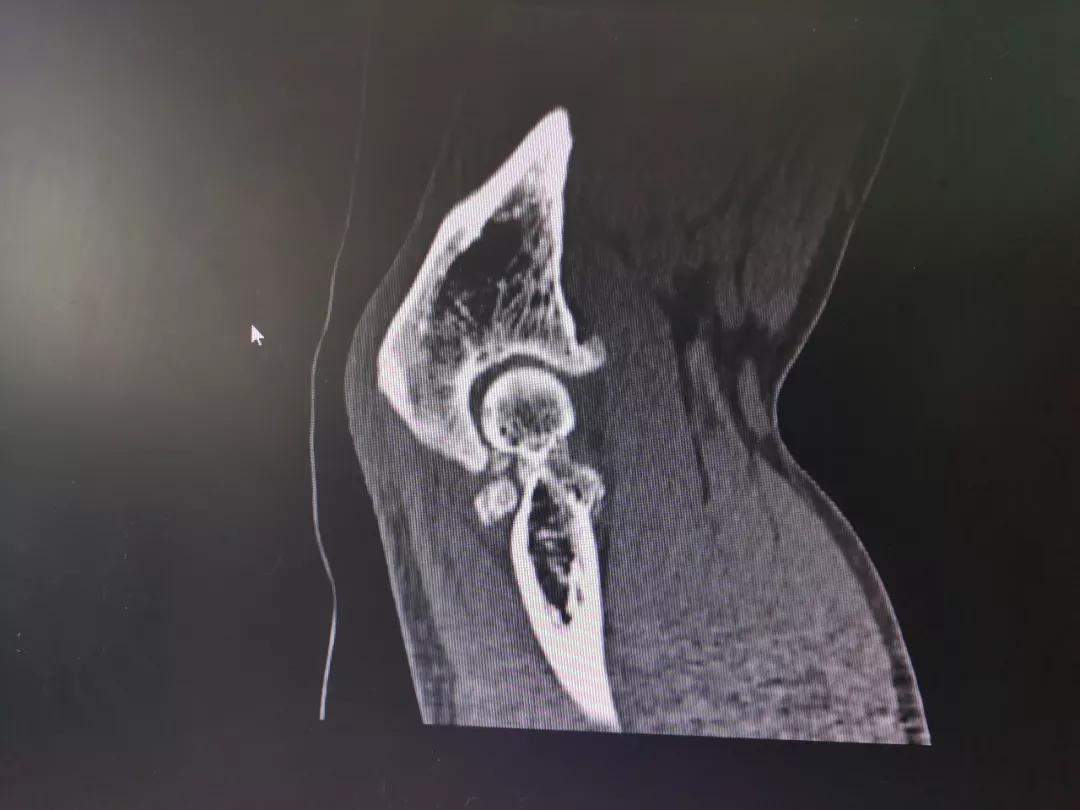

萝卜教授和同科室的莫捷华副主任医师根据陈叔肩部、肘部的X光片一起分析陈叔的病情,确诊是右肩袖损伤、右肘关节僵硬,经过讨论,一致决定给陈叔的肩、肘同时行两个部位的关节镜微创手术。

术前影像资料